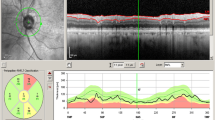

Patients underwent a comprehensive ophthalmological examination including measurement of best-corrected visual acuity (BCVA), assessment of intraocular pressure via Goldmann applanation tonometry, fundus examination, fundus autofluorescence imaging, and macular SD-OCT (version 1.5.12.0, Heidelberg Spectralis, Heidelberg Engineering, Inc., Germany). It has a 3.9-μm axial resolution and scans at 40,000 A-scans per second. For the peripapillary RNFL measurements, the RNFL exam protocol was used for scan acquisition, which was measured automatically by the existing software at a diameter of 3.45 mm around the centre of the optic disc after dilation of the pupil with 1% tropicamide. OCT analysis was performed in accordance with the APOSTEL recommendations for reporting quantitative optical coherence tomography studies [23]. All measurements were performed between 8 and 11 a.m. The same device was used for each patient. Since only high-quality pictures were included, there was no flawed segmentation of the peripapillary RNFL thickness measurements and therefore manual correction was not necessary. The global (G), temporal-inferior (TI, 270 to 315°), temporal (T, 315 to 45°), temporal-superior (TS, 45 to 90°), nasal-superior (NS, 90 to 135°), nasal (N, 135 to 225°), and nasal-inferior (NI, 225 to 270°) RNFL thickness measurements were recorded separately for each sector in micrometres (μm; Fig. 1). The pie charts in Fig. 1 are colour-coded according to percentiles as defined by the manufacturer leading to the following sector classifications: A green sector represents the area above the 5th percentile of the RNFL thickness distribution of eyes in the reference database (within normal limits). A yellow sector represents the area below the 5th percentile, but above the 1st percentile (borderline). A red sector represents the area below the 1st percentile (outside normal limits). The normative data provided by the manufacturer of the OCT device includes 201 healthy Caucasian patients (90/111 females/males) with a mean age of 48.2 ± 14.5 years (range 18 to 78 years) and a refractive error not exceeding + 5 or − 7 D sphere. Peripapillary RNFL thickness decreases slightly with age in healthy patients [24]. The reference database is therefore adapted to the age in order to take this tendency into account. In addition to the colour-coding, the pie charts illustrate the measured RNFL thickness of each sector (black numbers) compared to the age-correlated 50% percentile (green numbers). This age-correlated 50% percentile is calculated individually for each patient by the manufacturer software using the normative database described above. In Fig. 1B‴, for example, the measured RNFL thickness of 61 μm in the temporal sector (black number) is 16 μm thinner—defined in the following as “difference of peripapillary RNFL thickness”—than the age-correlated 50% percentile (77 μm, green number).

Incorrect peripapillary RNFL thickness measurement due to misalignment to the fovea. Data of an exemplary patient (ID4, see Table 1) are shown. (A) Incorrect measurement results of the peripapillary RNFL thickness due to an incorrect detection of the fovea, resulting in an incorrect thin peripapillary RNFL outside normal limits in the temporal-inferior area (A‴). (B) After manual correction of the optic disc-fovea angle (red arrow, B), the peripapillary RNFL thickness measurement was rotated by a corresponding number of degrees compared to the reference database (in the direction of the red arrows, B″), which resulted in measured normal RNFL thickness in the temporal-inferior area (B‴) and a measured thinner RNFL thickness of the temporal quadrant from 77 μm (A‴) to 61 μm (B‴). The age-correlated 50% percentiles of each sector, which are calculated individually for each patient by the manufacturer software using the normative database described in “Methods,” are illustrated in green numbers

If the fovea was not detected correctly by the Heidelberg Eye explorer software, the optic disc-fovea angle (ODFA) was manually corrected as described in Fig. 1 by the grader MR.